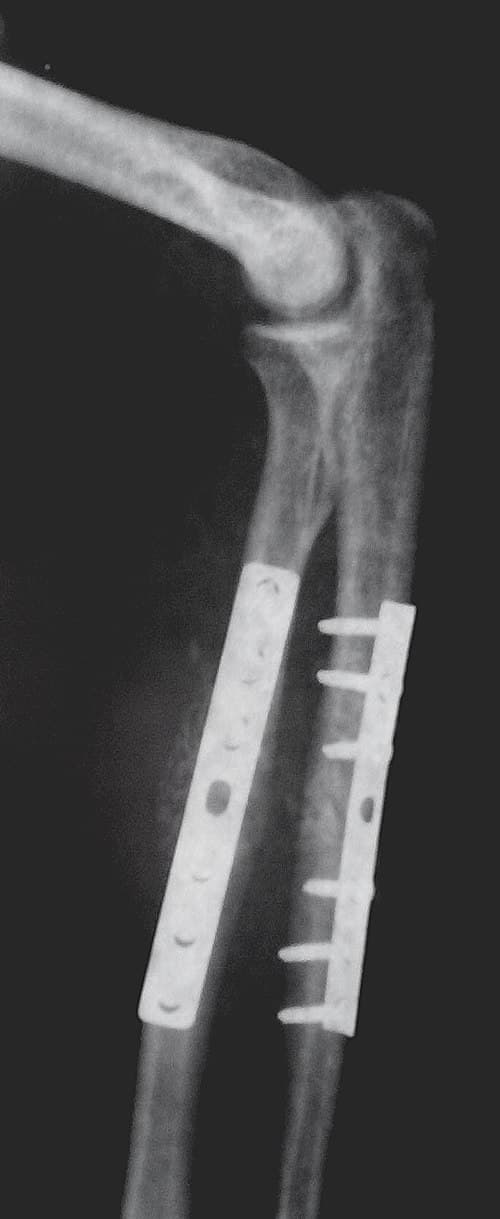

Internal fixation is an operation in orthopedics that involves the surgical implementation of implants for the purpose of repairing a bone, a concept that dates to the mid-nineteenth century and was made applicable for routine treatment in the mid-twentieth century. An internal fixator may be made of stainless steel, titanium alloy, or cobalt-chrome alloy. or plastics. Types of internal fixators include: Plate and screws Kirschner wires Intramedullary nails Open Reduction Internal Fixation (ORIF) involves the implementation of implants to guide the healing process of a bone, as well as the open reduction, or setting, of the bone. Open reduction refers to open surgery to set bones, as is necessary for some fractures. Internal fixation refers to fixation of screws and/or plates, intramedullary rods and other devices to enable or facilitate healing. Rigid fixation prevents micro-motion across lines of fracture to enable healing and prevent infection, which happens when implants such as plates (e.g. dynamic compression plate) are used. ORIF techniques often are used in cases involving serious fractures such as comminuted or displaced fractures or, in cases where the bone otherwise would not heal correctly with casting or splinting alone. Risks and complications may include bacterial colonization of the bone, infection, stiffness and loss of range of motion, non-union, mal-union, damage to the muscles, nerve damage and palsy, arthritis, tendonitis, chronic pain associated with plates, screws, and pins, compartment syndrome, deformity, audible popping and snapping, and possible future surgeries to remove the hardware. Closed Reduction Internal Fixation (CRIF) is reduction without any open surgery, followed by internal fixation. It appears to be an acceptable alternative in unstable distressed lateral condylar fractures of the humerus in children, but if fracture displacement after closed reduction exceeds 2 mm, open reduction and internal fixation is recommended. Various techniques of minimally invasive surgery for internal fixation of bones have been reported.